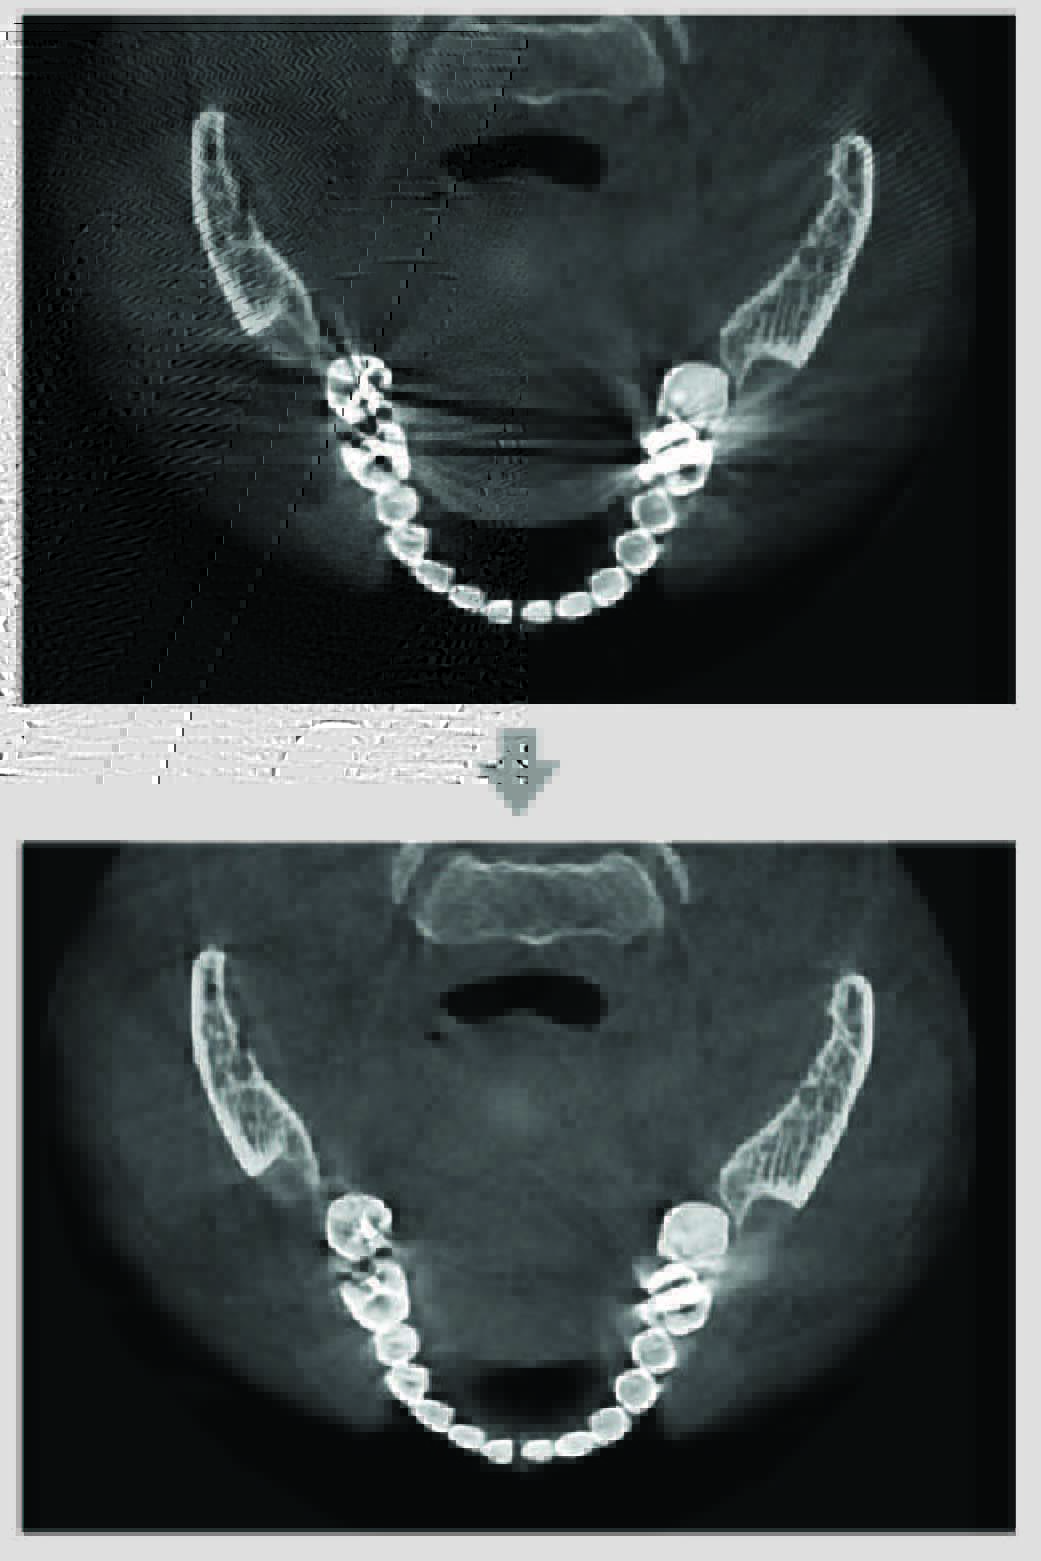

金屬散射抑制

SMARF功能 (Smart Metal Artifact Reduction Function)

可減低金屬散射帶來的影像扭曲